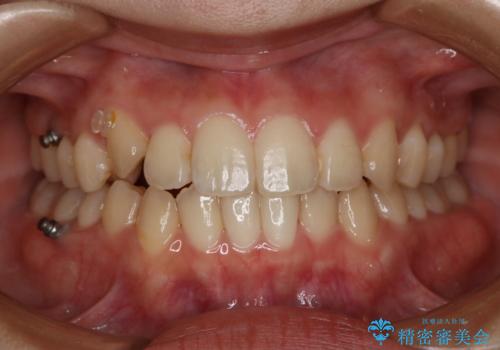

八重歯とクロスバイト:インビザライン治療

- 八重歯が気になるとの事でご相談にいらした方です。

インビザラインで綺麗に並べました。

気になっていた八重歯が綺麗になって大変喜んでいただけました。